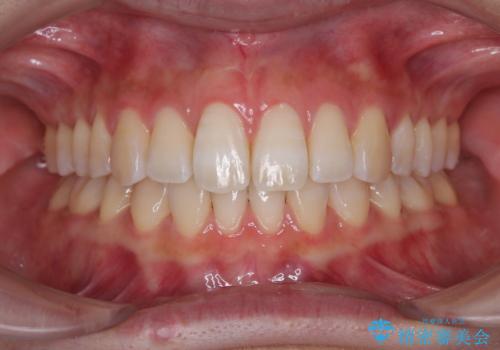

1年弱で治療方針を変更したため、治療期間は長くなりましたが、スペースは無事に閉じ、咬合の違和感なく仕上げることができました。

ただし、両方の臼歯部は理想的な咬合とは言えないため、咬合による歯の外傷を防ぐため、就寝時にはマウスピースを継続使用するようお願いしております。